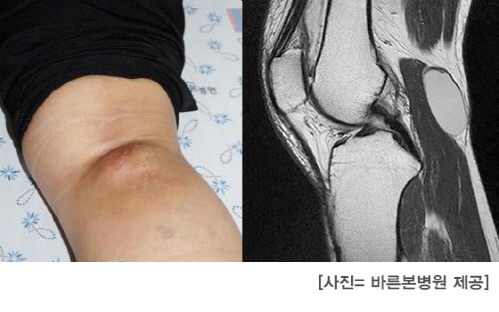

서울시 광진구에 거주하는 강자영(52·여)씨는 얼마 전 식당일을 하다 넘어져 무릎을 다쳤다. 이후 무릎 뒤 종아리의 위쪽 피부가 혹처럼 튀어나왔으며, 통증은 더욱 심해졌다. 결국 극심한 통증으로 병원을 찾은 결과 ‘베이커씨낭종(슬와낭종)’이라는 생소한 병을 진단받았다.

베이커씨낭종은 점액낭 안(연골 뒤편)으로 이동한 관절액이 무릎 뒤쪽으로 밀려나면서 슬와부에 물혹이 발생하는 질환이다. 혹이 무릎 뒤에 생기는 이유는 관절막이 약하기 때문이다. 퇴행성 관절질환을 앓는 40대 이후 여성에서 가장 흔하게 발생하며, 반월상연골판 손상이나 십자인대 파열 등 무릎관절질환과 동반될 때가 많다. 무릎관절은 슬개골이 있는 앞부분인 슬개부와 뒷부분인 슬와부로 나뉜다.

이 질환을 앓으면 앉을 때 압박감이나 통증이 느껴지게 된다. 혹 크기가 큰 경우에는 주위 신경을 눌러 신경마비가 나타날 수도 있다. 무릎을 무리하게 사용하거나 외부충격이 가해지면 무릎관절에 물이 더 차게 되는데 이런 경우 물혹의 크기가 증가하면서 통증은 더욱 심해진다.